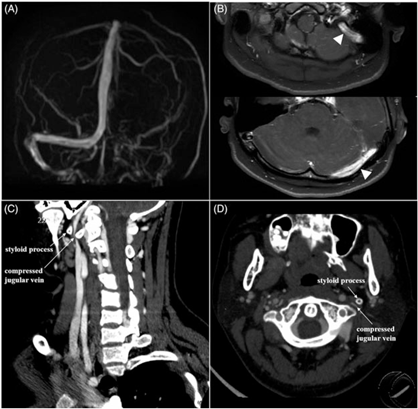

A 15-year-old teenager presented with a 2-month history of headache. Neurological examination was normal except for papilledema. Further lumbar puncture indicated intracranial hypertension (330 mm H2O). Brain magnetic resonance imaging (MRI) was normal but phase contrast-magnetic resonance venography (PC-MRV) (Figure 1(A)) suggested possible left transverse-sigmoid sinus thrombosis; subsequent contrast-enhanced 3D fat-saturated T1 volumetric isotropic turbo spin echo acquisition (VISTA) MRI (Figure 1(B)) confirmed the pathology. Hyper-coagulable panel results (including six steroid sex hormones, antithrombin III, protein C, protein S, lupus anticoagulant, and anticardiolipin antibodies) were all within normal range. In further examination, computed tomography (CT) venography images (Figure 1(C) and (D)) showed that the left jugular vein was compressed by the styloid process, consistent with Eagle syndrome.Reference Badhey, Jategaonkar and Anglin Kovacs1 The patient who refused the recommended surgical treatment, however, chose anticoagulant therapy consisting of low-molecular weight heparin subcutaneous injection in addition to new oral anticoagulant. At 18-month follow-up, the patient reported no symptoms remained.

Figure 1: Neurological imaging examinations of the patient. PC-MRV (A) showed absent signal in the left transverse-sigmoid sinuses. Contrast-enhanced 3D fat-saturated T1 VISTA MRI (B; white arrowheads) demonstrated gadolinium enhancement of the left transverse-sigmoid sinuses, indicating chronic venous sinus thrombosis. The curved planar reformation (CPR) and axial source images from CT venography images (C and D; white arrow) showed styloid process compressing the left jugular vein.